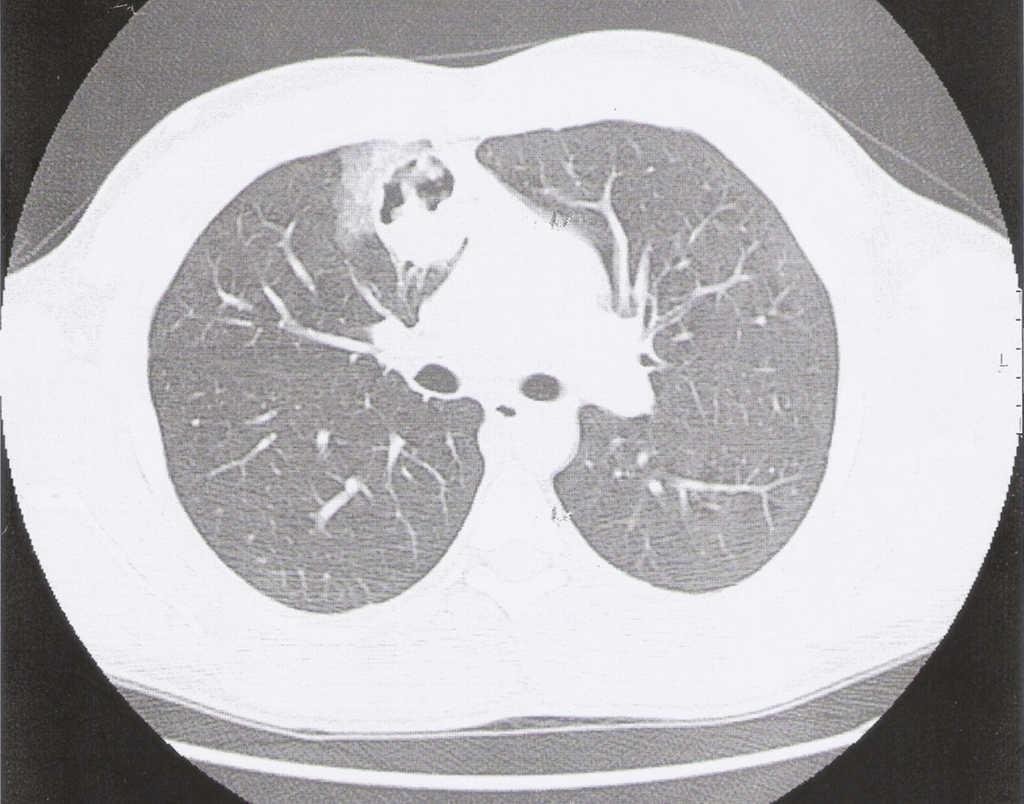

A 24-year-old man, a non-smoker, presented at the emergency department with complaints of cough, haemoptysis, dyspnoea on exertion, fever (38 °C) and excessive sweating at night, with two days of evolution. He had no relevant pathologic background, and physical examination was normal. On the chest X-ray we found a right infrahilar shadow, the bronchoscopy was normal as were the respiratory function and the blood tests. The first computed tomography (CT) of the chest showed a 44 mm heterogeneous (well-circumscribed and probably cavitated) ovoid mass (Figure 1), located in the inner right upper lobe, near the middle lobe. The differential diagnosis was lung abscess, round pneumonia, pulmonary tuberculosis, aspergilloma and tumour. After a 3-week course of antibiotics, a second CT, now with intravenous iodinated contrast, showed a homogenous mass of the same size and location, and the patient was transferred for surgical evaluation, and resection of the right upper and middle lobe. Histopathological examination revealed spindle cell proliferation, with storiform or fascicular pattern, with foci of haemorrhage, inflammatory infiltrate of lymphocytes, neutrophils, eosinophils and aggregates of foam cell (Figure 2). Rare Touton giant cells were also found. No significant cytological atypia was identified. The neoplastic cells were diffusely and strongly positive for immunostaining for ALK and histiocytic marker CD163, while weakly and focally positive for smooth muscle marker SMA and cytokeratin CAM5.2.

Figure 2. Spindle cells with storiform or fascicular pattern, haemorrhage and inflammatory infiltrate, including foam cells. There is a residual bronchial structure (HE, 100×).